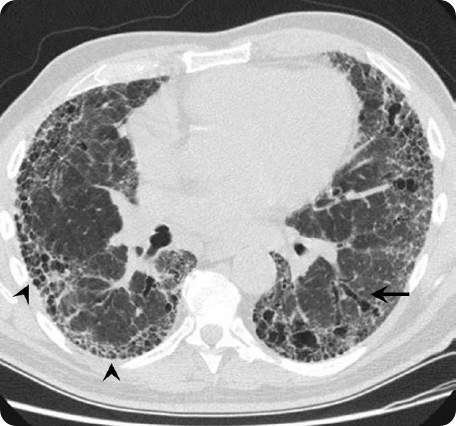

HRCT scan

HRCT scan of an IPF patient. Adapted from Meltzer & Noble Orphanet Journal of Rare Diseases 2008.